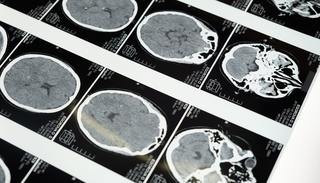

大多数重大脑疾病都源于脑功能网络的病变,但普遍缺乏有效治疗手段,关键原因在于对人类脑功能网络和疾病相关神经环路的检测非常困难,严重阻碍了对脑疾病机制的理解。迄今为止,在人类生命体的研究中获诺贝尔奖最多的是脑科学,但大脑这个由上千亿神经细胞组成的器官与人体的关联至今还未被完全参透。

由于对病源和疾病发展学方面知识不足,许多大脑疾病目前仍属不治之症。通过深入了解大脑相关机制和作用过程,科学家正试图将这些发现转换成治疗人类生理和心理病痛手段上的突破。这其中主要包含精神类疾病和脑部退化性疾病。

包括抑郁症、情绪问题、长期疼痛、精神分裂等在内的精神力疾病对认知和情感能力造成损害,并且会严重影响患者应对生活的能力。脑部退化性疾病则包含了老年痴呆症、帕金森综合症、震颤性麻痹和运动神经元疾病等对病患身体活动能力伤害巨大的疾病。